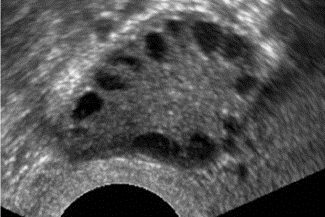

Unauffällige oviarielle Reserve, AFC 8

Reduzierte ovarielle Reserve, AFC 2

AFC erhöht bei PCOS, ACF > 15